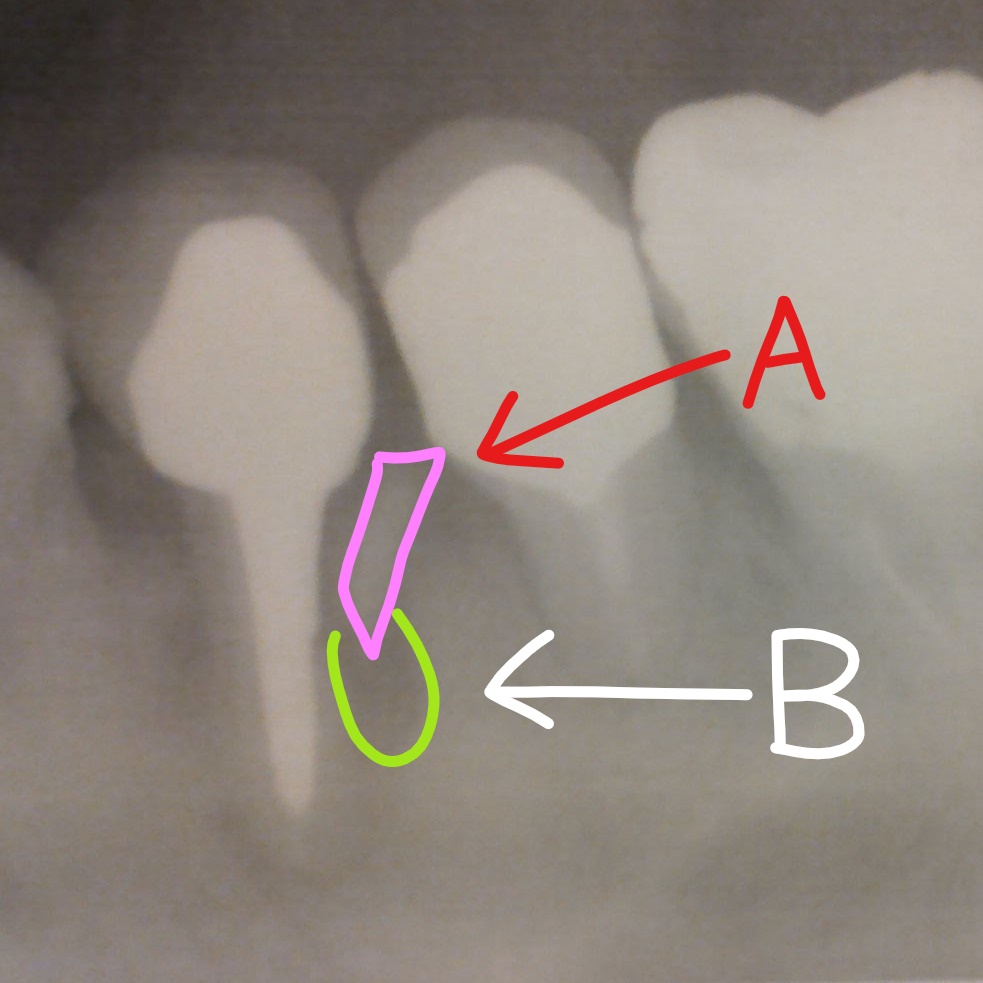

A:突き出た歯根の欠片

B:バイキンの巣

幸いなことに 8月に3針縫う手術を受けて、この歯は回復した。

(病巣を切除して、根を補強してもらった)